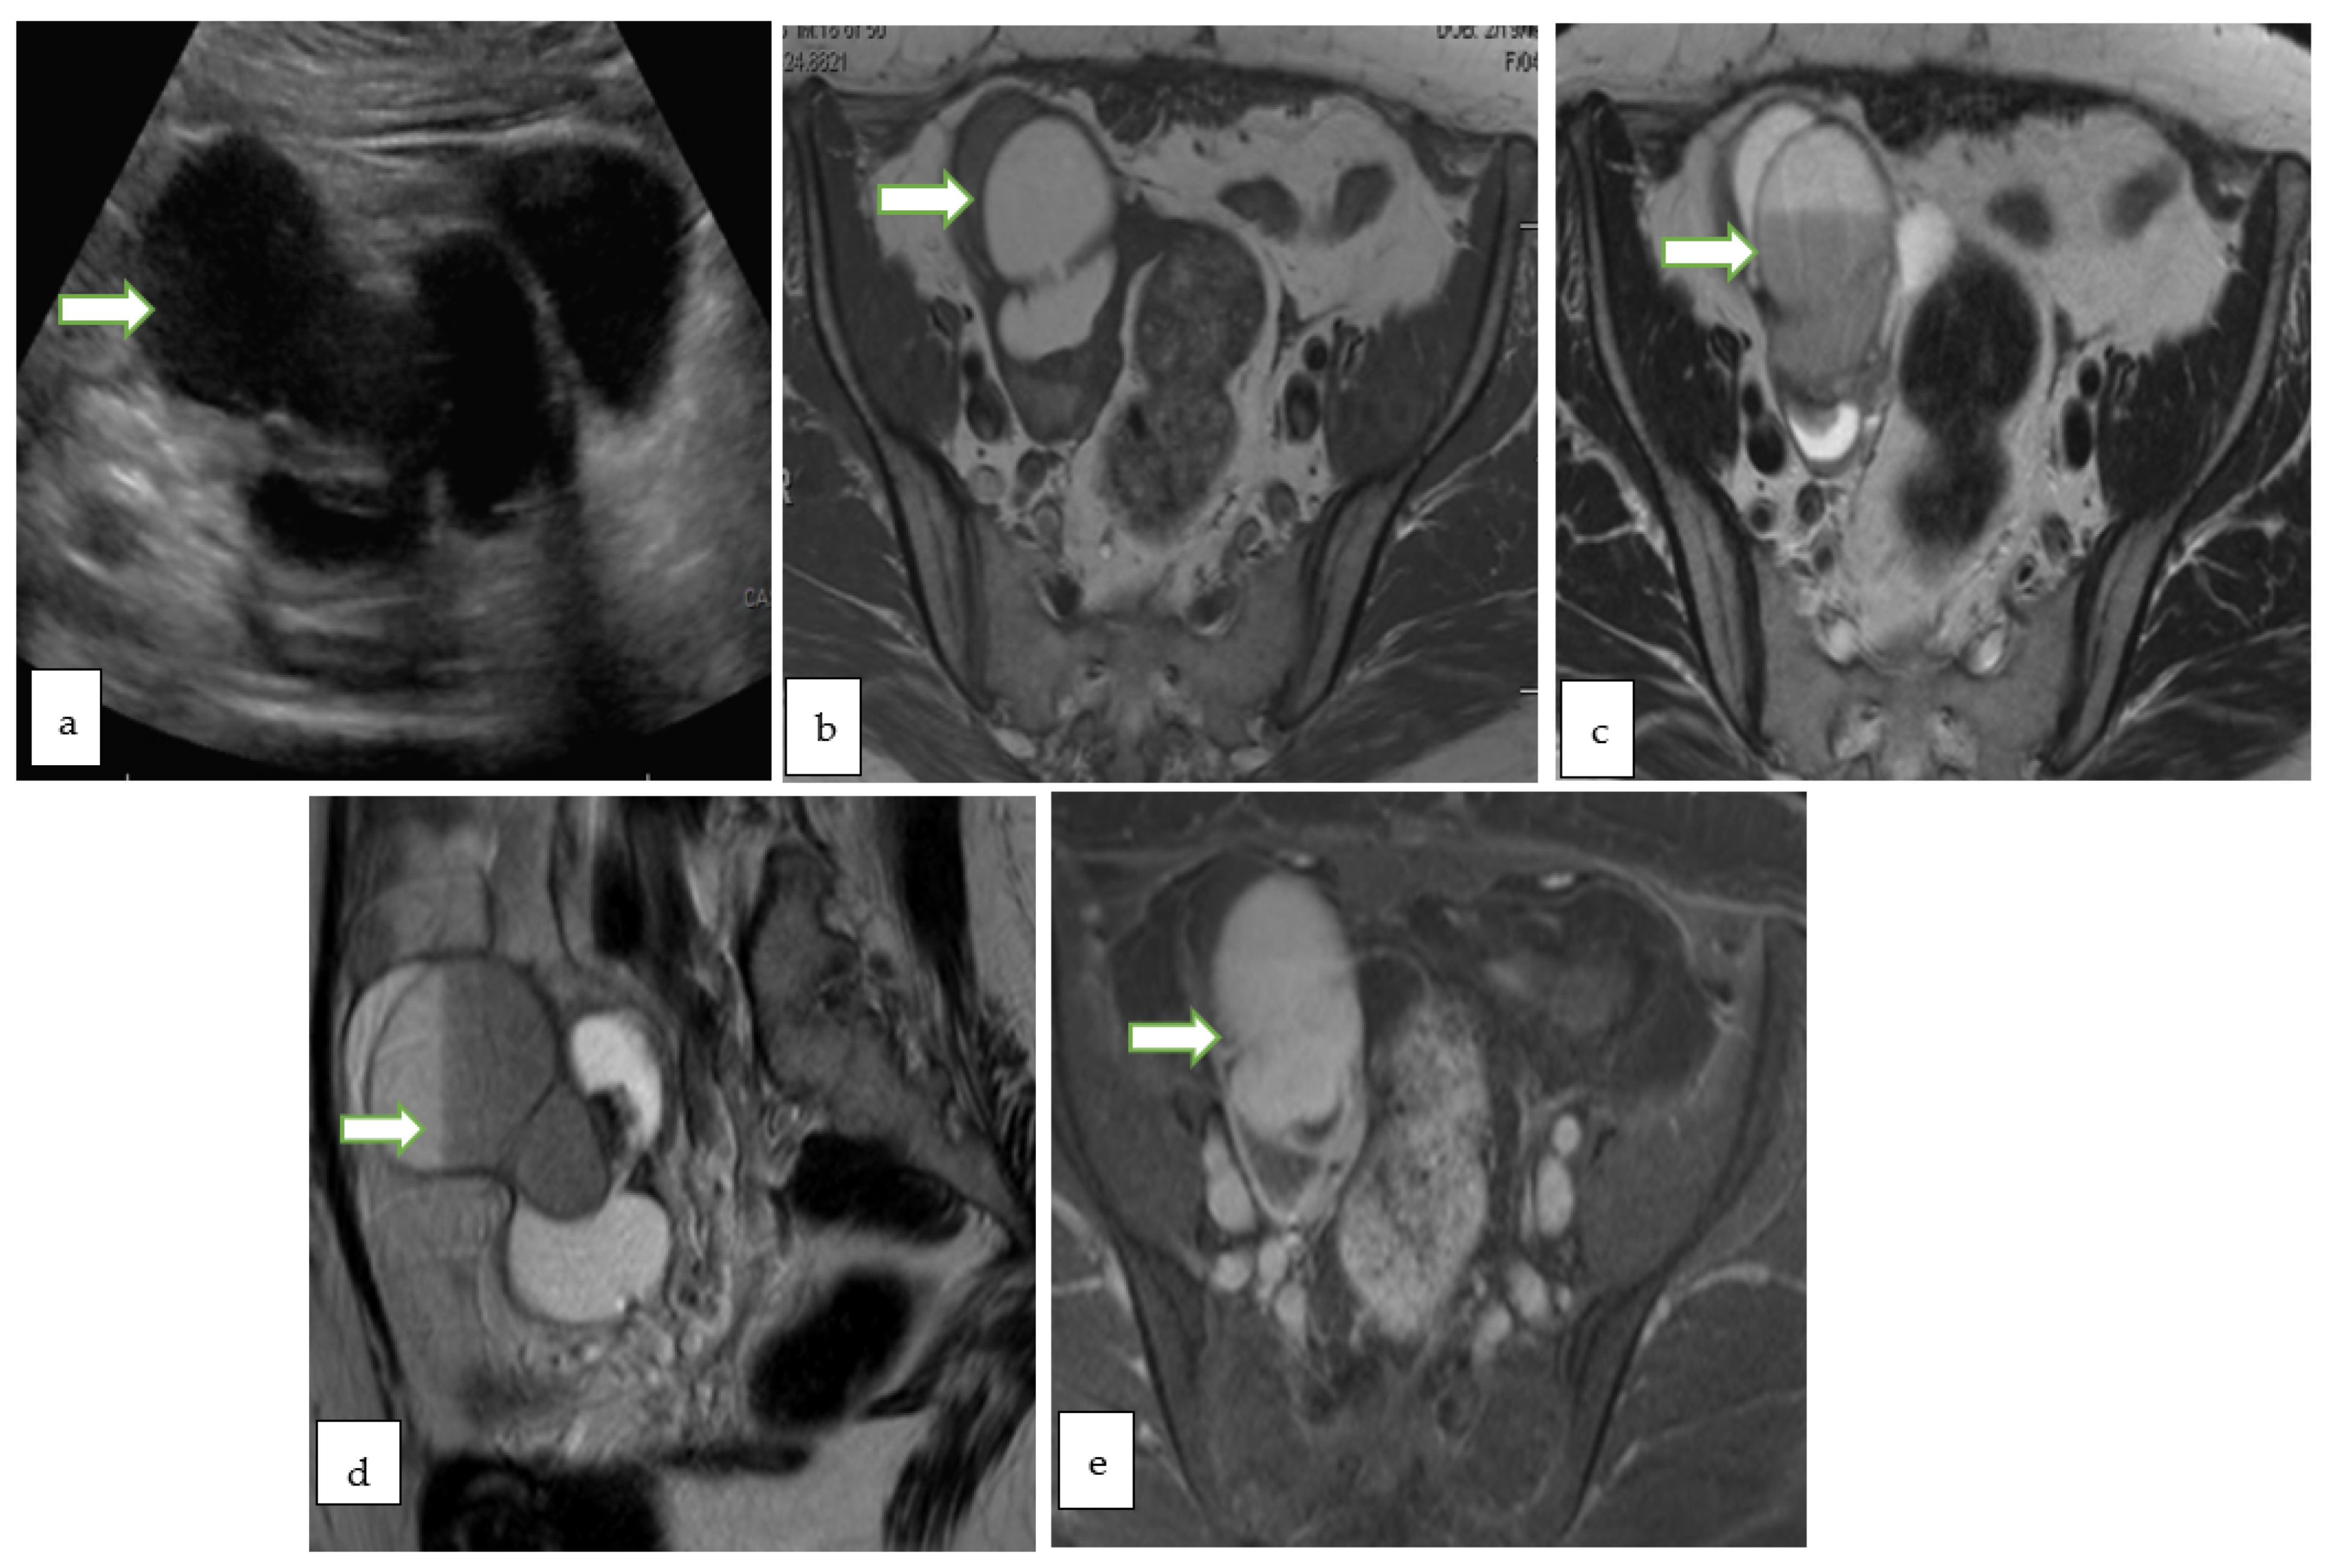

4.2. Magnetic Resonance Imaging (MRI)

- Thomassin-Naggara, I.; Poncelet, E.; Jalaguier-Coudray, A.; Guerra, A.; Fournier, L.S.; Stojanovic, S.; Millet, I.; Bharwani, N.; Juhan, V.; Cunha, T.M.; et al. Ovarian-Adnexal Reporting Data System Magnetic Resonance Imaging (O-RADS MRI) Score for Risk Stratification of Sonographically Indeterminate Adnexal Masses. JAMA Netw. Open 2020, 3, e1919896. [Google Scholar] [CrossRef]

- Sadowski, E.A.; Thomassin-Naggara, I.; Rockall, A.; Maturen, K.E.; Forstner, R.; Jha, P.; Nougaret, S.; Siegelman, E.S.; Reinhold, C. O-RADS MRI Risk Stratification System: Guide for Assessing Adnexal Lesions from the ACR O-RADS Committee. Radiology 2022, 303, 204371. [Google Scholar] [CrossRef]

| O-RADS MRI Score | Risk Category | Positive Predictive Value for Malignancy | Lexicon Description |

| 3 | Low risk | ~5% | Cyst: Unilocular–proteinaceous, hemorrhagic or mucinous fluid content - Smooth enhancing wall - No enhancing solid tissue |

| Cyst: Multilocular-Any type of fluid, no lipid content - Smooth septae and wall with enhancement-No enhancing solid tissue | |||

| Lesion with solid tissue (excluding T2 dark/DWI dark) - Low risk time intensity curve on DCE MRI | |||

| Dilated fallopian tube - Non-simple fluid: Thin wall/folds - Simple fluid: Thick, smooth wall/folds - No enhancing solid tissue | |||

| 4 | Intermediate risk | ~50% | Lesion with solid tissue (excluding T2 dark/DWI dark) - Intermediate risk time intensity curve on DCE MRI - If DCE MRI is not feasible, score 4 is any lesion with solid tissue (excluding T2 dark/DWI dark) that is enhancing ≤ myometrium at 30–40 s on non-DCE MRI |

| Lesion with lipid content - Large volume enhancing solid tissue | |||

| 5 | High risk | ~90% | Lesion with solid tissue (excluding T2 dark/DWI dark) - High risk time intensity curve on DCE MRI - If DCE MRI is not feasible, score 5 is any lesion with solid tissue (excluding T2 dark/DWI dark) that is enhancing > myometrium at 30–40 s on non-DCE MRI |

| Peritoneal, mesenteric or omental nodularity or irregular thickening with or without ascites |